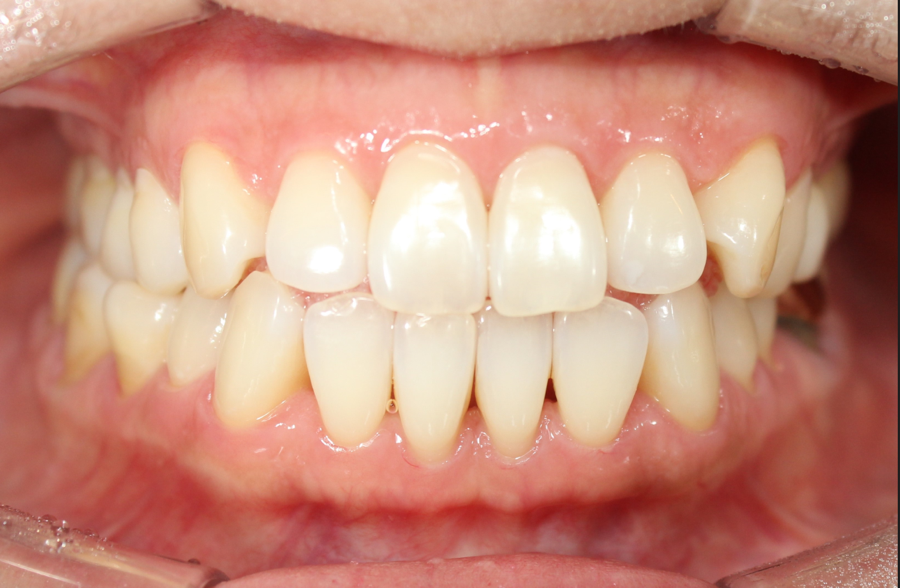

본 환자분은 중년의 여성분으로

배열보다도

오른쪽치아가 먼저 닿은 후 미끄러져서

얼굴이 비뚫어지고 턱이 불편하다

는 이유로 교정을 시작하셨습니다

1년여 정도 되었을까요

비대칭이 개선되고

위아래 중심선이 맞아졌습니다

자 오늘은 치아 문제로 생긴 비교적 간단하게 해소된 비대칭의 캐이스를 살펴보았습니다.

중년의 교정이라 환자분 고민하다가 결정하셨지만 비발치로 빠르게 마무리 되어가서 지금은 큰 만족을 하고 계셔서 이럴땐 저도 같이 기쁩니다.